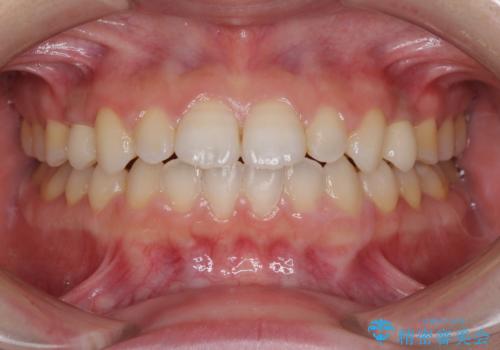

欠損と残存乳歯 矯正治療とインプラント治療